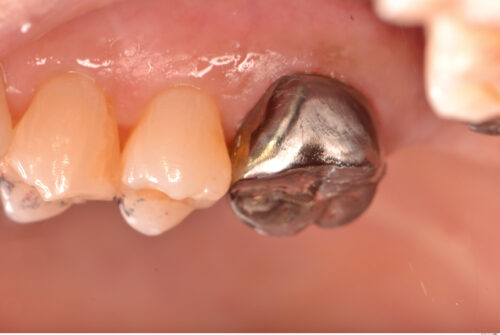

60代女性。3年前に他院にて自費治療で入れたセラミックの詰め物が取れたのでつけて欲しいとのことで来院。

保険適用のチタンクラウンで修復しました。